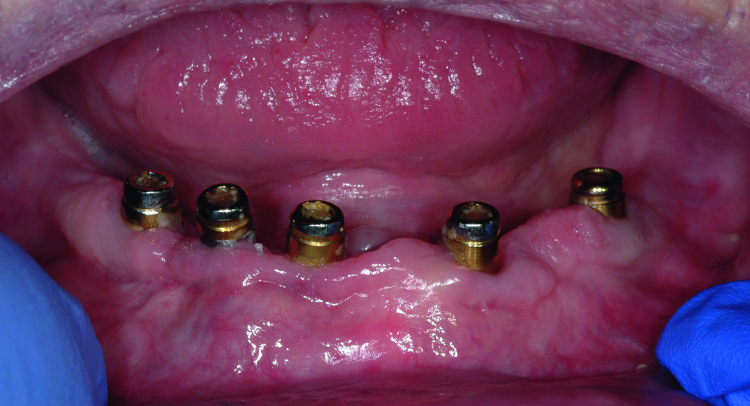

Fig. 2: Clinical image of patient. Note the wear of the metal abutments due to disengagement of the nylon retention inserts as a result of fulcrum during function.

The patient continued to experience problems with the lower denture coming loose during function and required frequent replacement of the nylon male inserts; replacement with Extended Range inserts did not vary performance. The metal abutments demonstrated considerable wear as well (Fig. 2). Relining the lower denture did not improve the performance of the anchor system.